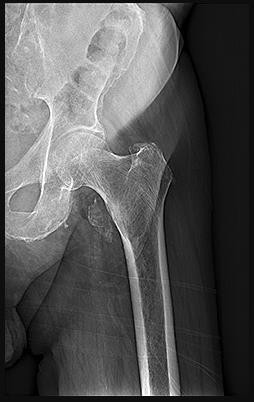

Question 7:

A 45-year-old trauma patient sustains an intra-articular distal femur fracture. Advanced imaging identifies a coronal plane fracture of the lateral femoral condyle (Hoffa fragment). Biomechanical studies suggest which of the following screw orientations provides the most rigid fixation for this specific fracture pattern?

Correct Answer: Posteroanterior oriented lag screws

Explanation:

A Hoffa fracture is a coronal plane fracture of the femoral condyle, more commonly affecting the lateral condyle. Biomechanical studies have demonstrated that posteroanterior (PA) directed lag screws provide superior stability and higher load to failure compared to anteroposterior (AP) directed screws. While AP screws are often used clinically due to ease of placement via an anterior approach, PA screws are biomechanically advantageous because they enter through thicker cortical bone posteriorly and are directed perpendicular to the fracture plane.